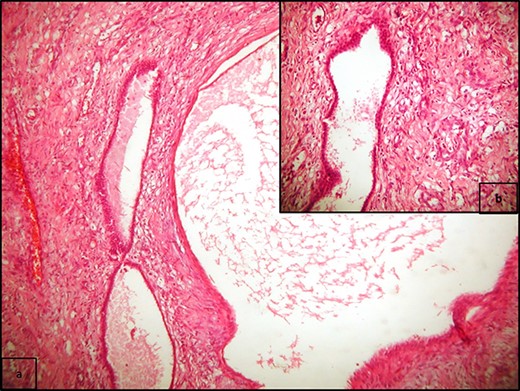

A 20-year-old Caucasian woman presented herself to the outpatient department because of a mass on the left kidney. The mass was an incidental finding in an abdomen computed tomography (CT), which was suggested within the diagnostic evaluation for a persistent flank pain. In the past, she never had any pathologic urologic situation. According to the CT finding, the mass was located on the lower pole of the left kidney (83 × 111 × 111mm) and there was no other pathologic finding. Anamnestically, she had heterozygous beta Mediterranean anaemia. The patient was obese (body mass index = 33.4 kg/m2). We proceeded with a thorax CT which revealed no pathology. The patient underwent a laparoscopic nephrectomy by an urologist well trained and experienced in laparoscopy. Macroscopically, a mass in the lower pole of the left kidney (110 × 100 × 100 mm) was documented. Cut sections revealed multiple thin walled, non-communicating cysts of varying sizes with smooth lining without solid component. Microscopically, the tumor was characterized of cysts separated by thin septa. The cysts lined by single layer of flat, cuboidal and hobnail epithelium and the septa were fibrous, hypocellular to hypercellular. No mitoses or necrosis were identified. The immunohistochemical examination showed that the epithelial cells were positive for the cytokeratins AE1/AE3 and PAX-8. The stromal cells were positive for the progesterone receptors, estrogen receptors and CD10. The latter was concentrated around epithelial elements (Figs 1 and 2). These findings established the diagnosis of ACN. At the 12-month follow-up control with abdomen CT, there was no pathologic finding (Fig. 3). The patient is under urologic and nephrologic montitoring without any abnormal finding at 21 months after surgery. This research complies with the guidelines for human studies and was conducted ethically in accordance with the World Medical Association Declaration of Helsinki.

(a) Multiple cysts of varying sizes separated by septa; flat epithelial cells lining the cysts, and there is no atypia or mitosis (H/E x400); (b) cysts separated by hypercellular stroma (H/E x100).